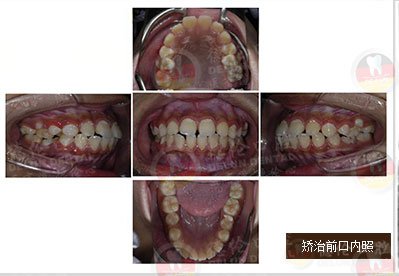

女 13岁

牙齿症状:上下前牙前突、唇倾,上下牙弓散在间隙

矫治方法:SPEED矫治器结合种植钉、整体内收上下牙弓、改善双牙弓前突以及凸面型侧貌